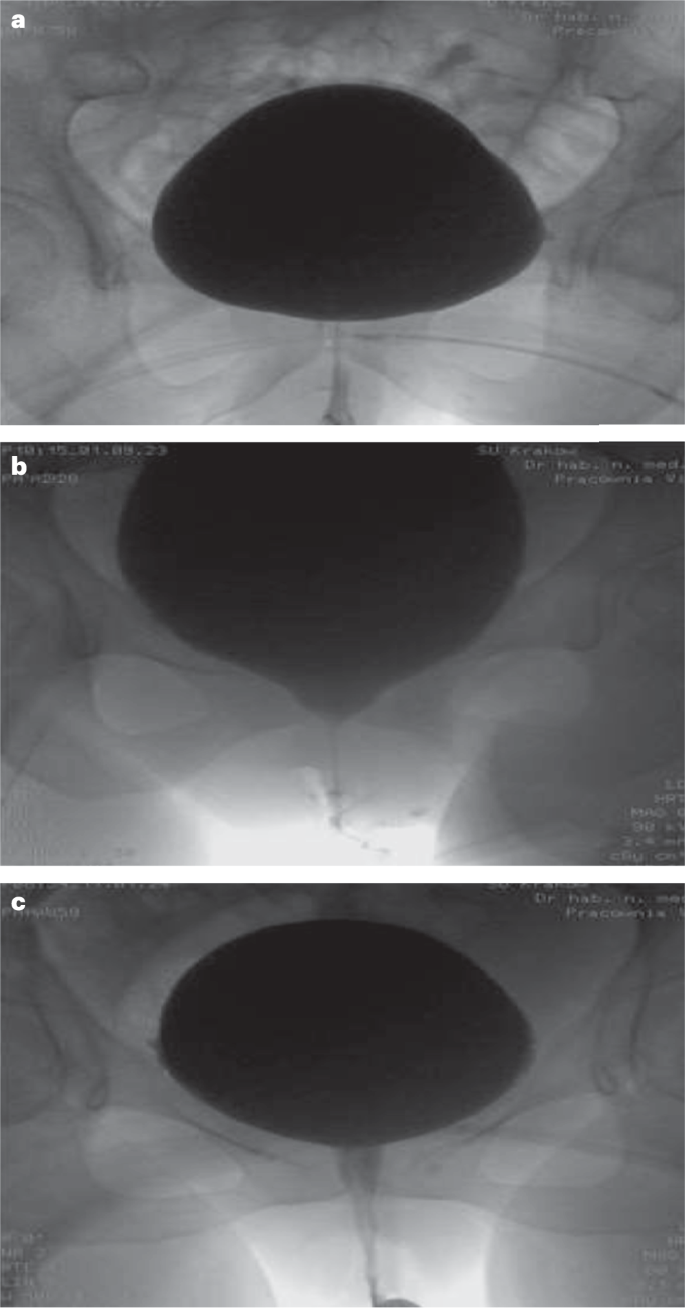

Videourodynamics — role, benefits and optimal practice | Nature Reviews  Urology Hab p pal By Nature